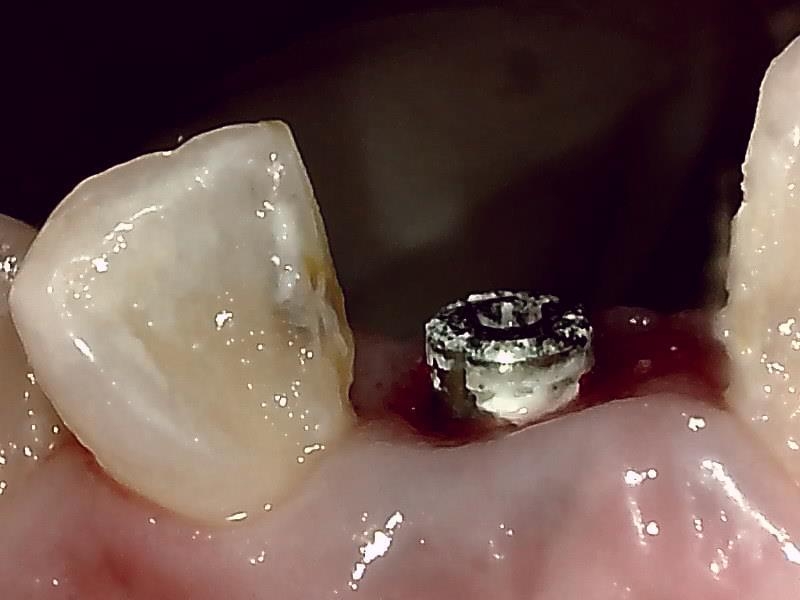

アバットメント装着 (右上)

アバットメントの装着している状況です。

アバットメント装着